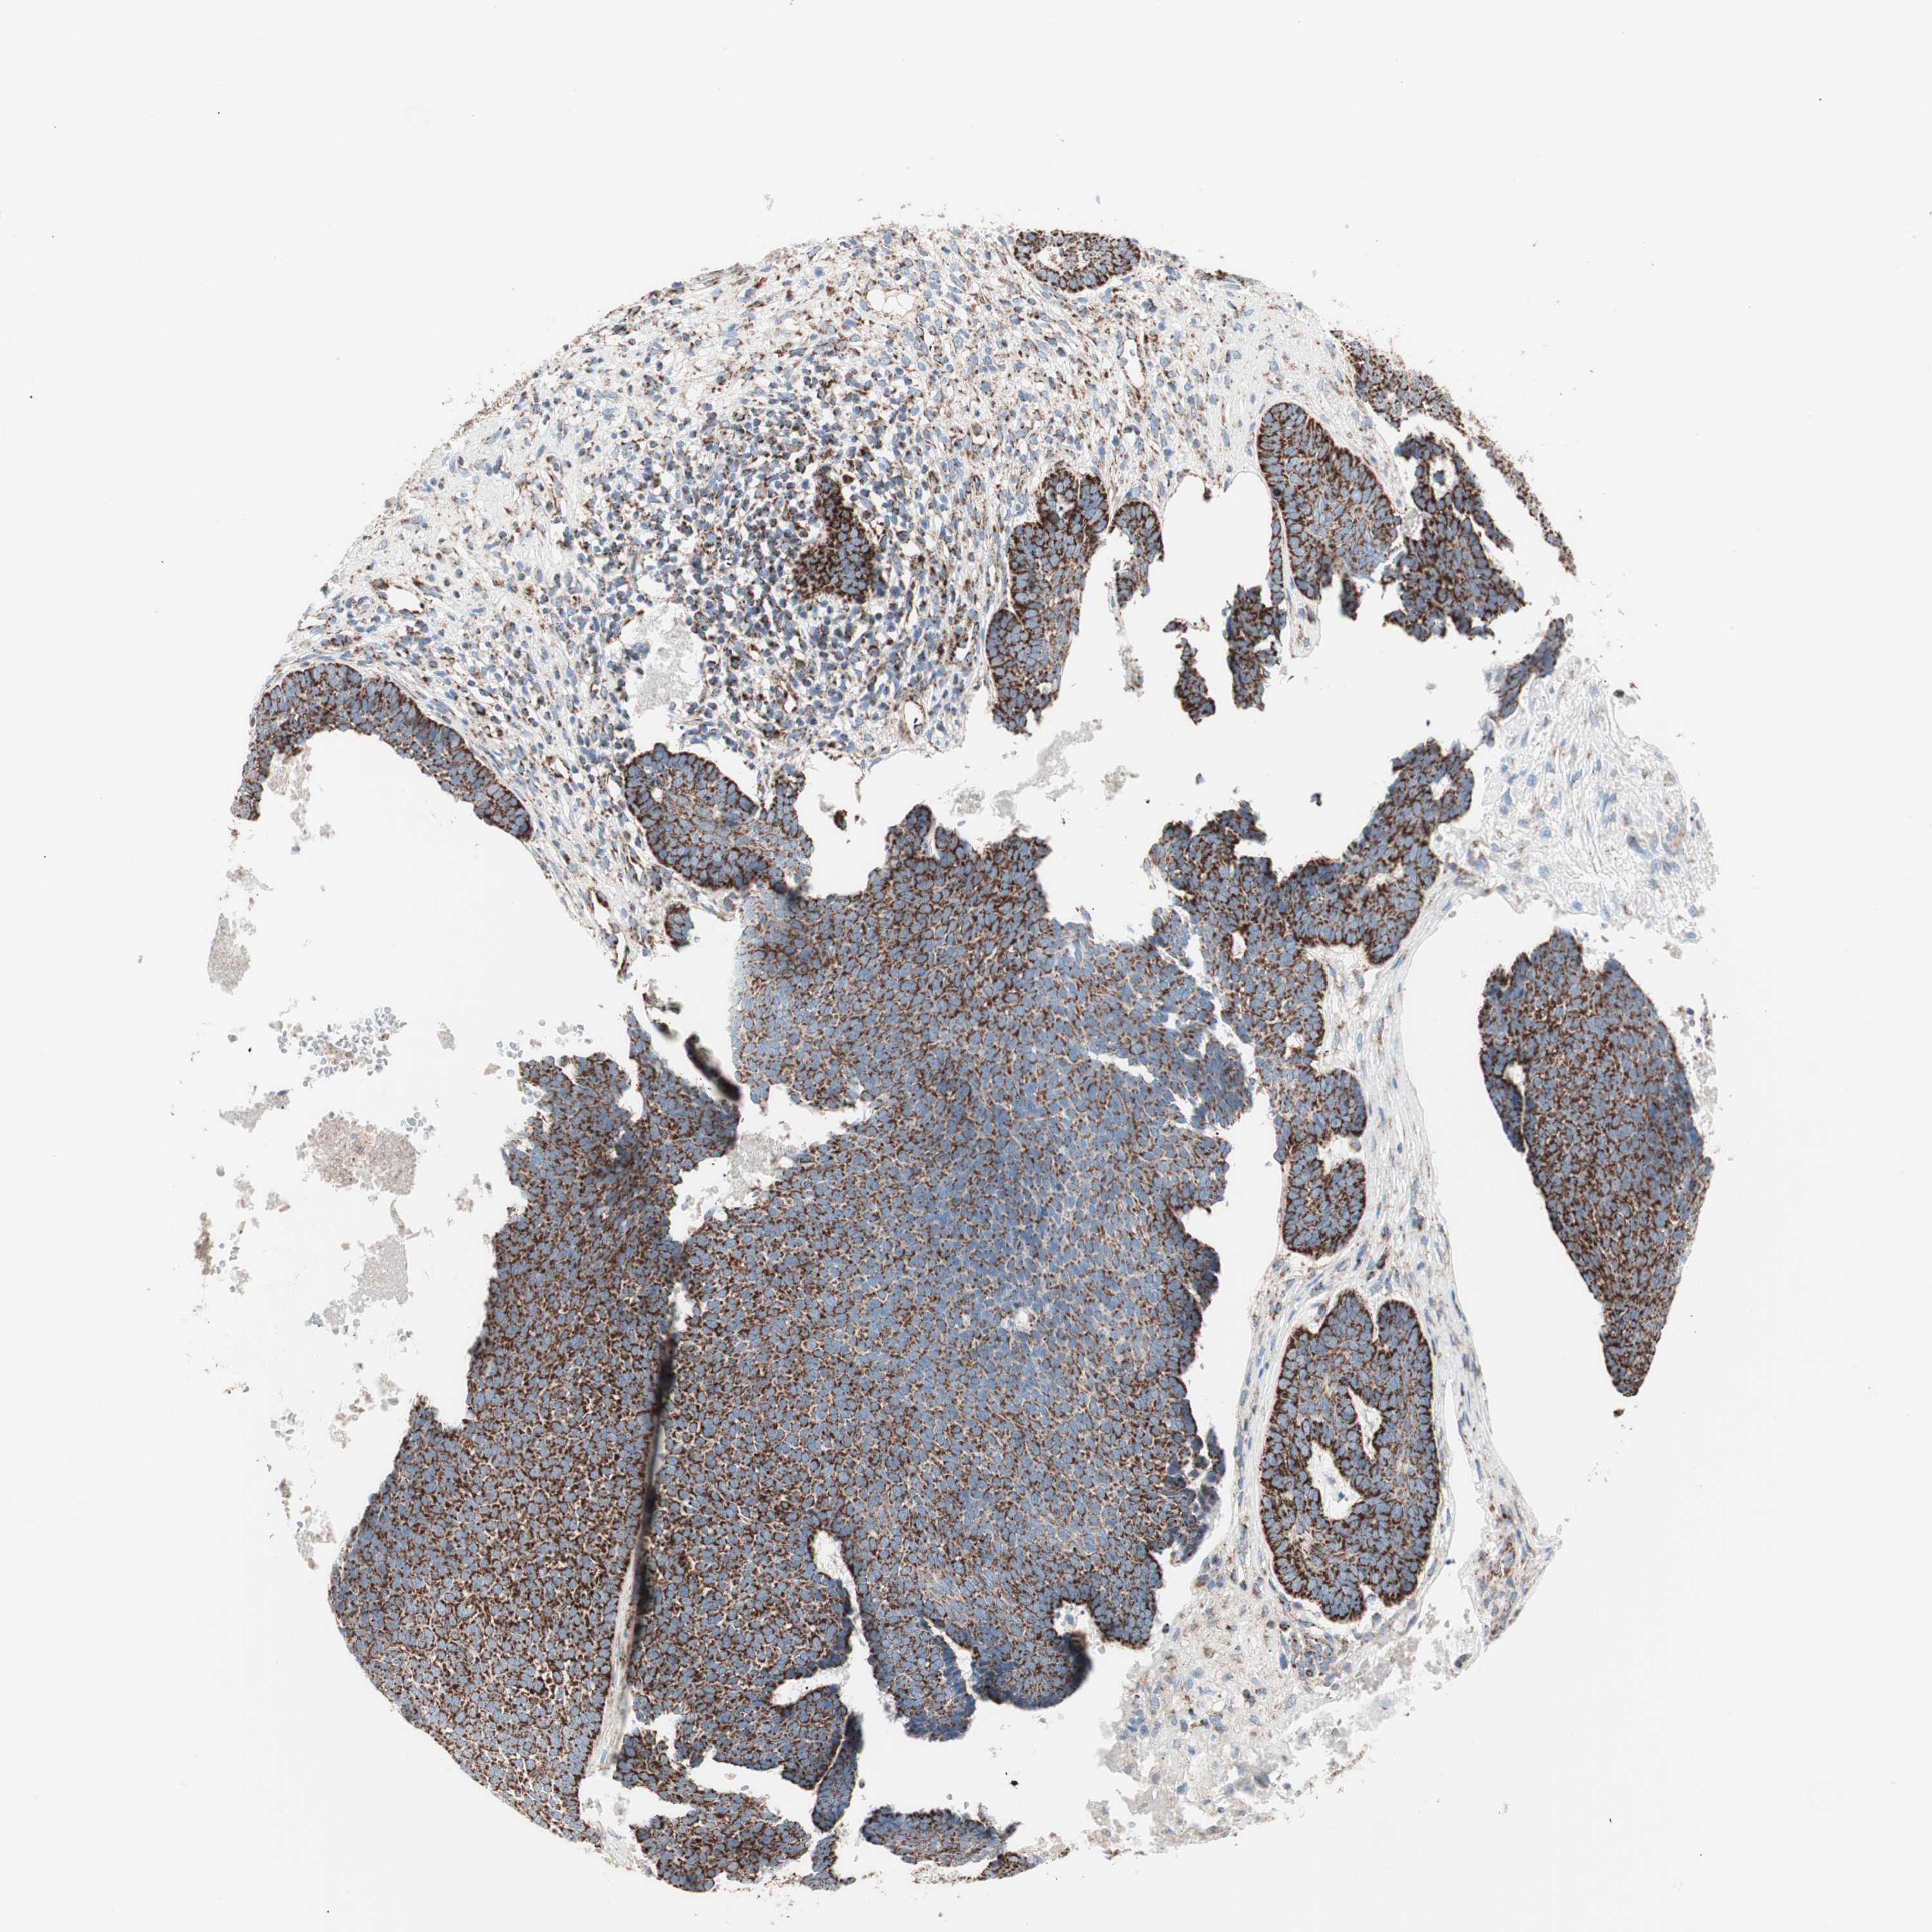

SKIN CANCER - Protein expressioni

A mouse-over function shows sample information and annotation data. Click on an image to view it in a full screen mode. Samples can be filtered based on level of antibody staining by selecting one or several of the following categories: high, medium, low and not detected. The assay and annotation is described here.

Antibody stainingi

Antibody staining in the annotated cell types in the current human tissue is reported as not detected, low, medium, or high, based on conventional immunohistochemistry profiling in selected tissues. This score is based on the combination of the staining intensity and fraction of stained cells.

Each image is clickable and will lead to virtual microscopy that enables deeper exploration of all samples and also displays staining intensity scores, fraction scores and subcellular localization as well as patient and tissue information for each sample.

Antibody HPA011562

Squamous cell carcinoma, NOS

Basal cell carcinoma

Squamous cell carcinoma, metastatic, NOS

Papilloma, NOS